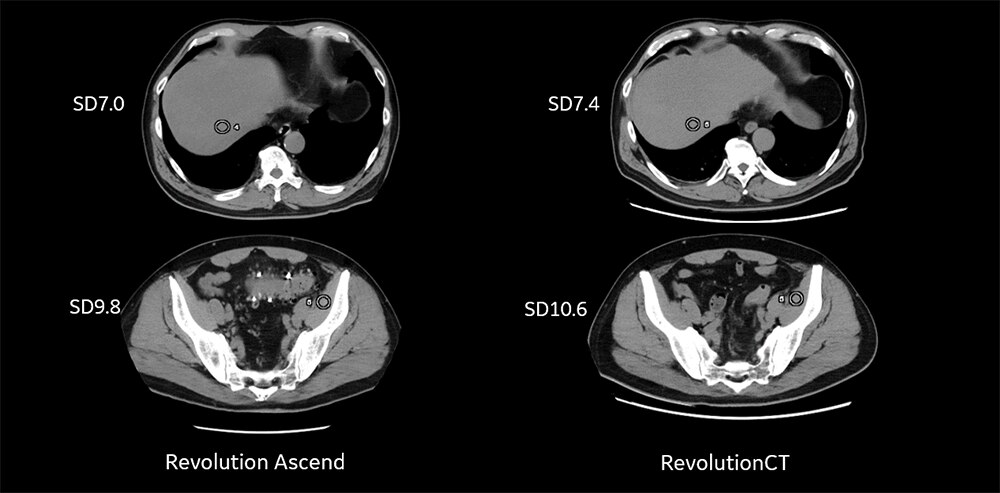

その結果、従来CTと比較してmAの頭打ちが起こりやすい大きい体格の患者様において、SDが目標NIに等しく良好な画像を得ることができました。実際に、大動脈弓部~肝臓下縁までのmAを確認すると、従来CTでは頭打ちがおこっているのに対し、AscendではAuto Prescriptionによって自動で回転時間が1秒に変更されたため、頭打ちが起こらず適切なmAを使用することができていることがわかります。(Fig6)

Fig5. 従来CTとRevolution Ascendでの体格が大きい方の腹部画像

Fig6. Fig4の撮影における管電流の推移(横軸:スライス位置 縦軸:管電流)

大動脈弓部~肝臓下縁までの管電流の推移。従来CTではピッチ1.375、回転時間0.4秒で撮影、通常Ascendではピッチ1.375、回転時間0.6秒で撮影しておりますが今回Auto Prescriptionにより、自動で回転時間1秒が選択されました。従来CTではほぼ頭打ちしていますが、Ascendでは回転時間の自動調整で頭打ちを防ぐことができていることがわかります。